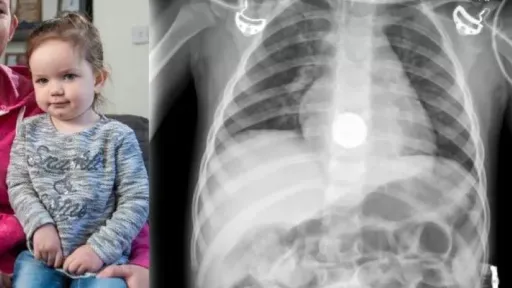

Un copil de 2 ani a înghițit o baterie și a ajuns la spital. Cazul a avut loc zilele trecute în orașul Krasnogorsk din Rusia.

Copilul a fost internat de urgență, când a început să respire anormal și să saliveze abundent. Medicii au început să o examineze pe fată și au aflat că bateria înghițită era blocată în esofag.

„Datorită prezenței prelungite a bateriei în interiorul tractului gastrointestinal, fetița a dezvoltat necroză a peretelui esofagian. Este important ca părinții să știe: dacă un copil a înghițit un obiect străin, este necesar să se solicite imediat ajutor medical. Nu ar trebui să încercați să-l scoateți pe cont propriu sau să așteptați ca acesta să iasă singur”, spune medicul endoscopist Ivan Michurin, conform presei locale.

Sunt deosebit de periculoase bateriile care, la oxidare, pot provoca o arsură electrochimică și pot duce la consecințe ireversibile, până la perforarea peretelui esofagian.